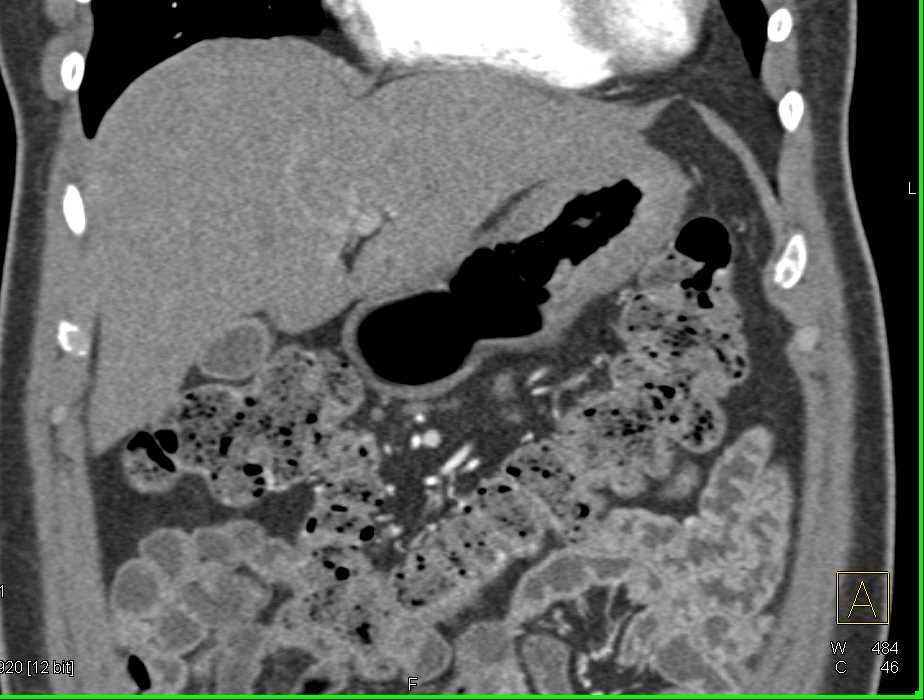

Gastric GIST Tumor